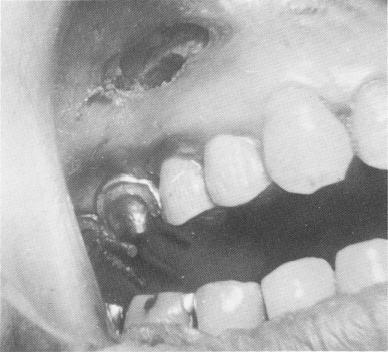

Fig. 15-63. The pin implants extended through the scalloped template. High up in the maxillary tissue is seen the exposed bone and area where the apicoectomy was per-formed.

3 Endosseous pin implants extend through scalloped template in maxilla